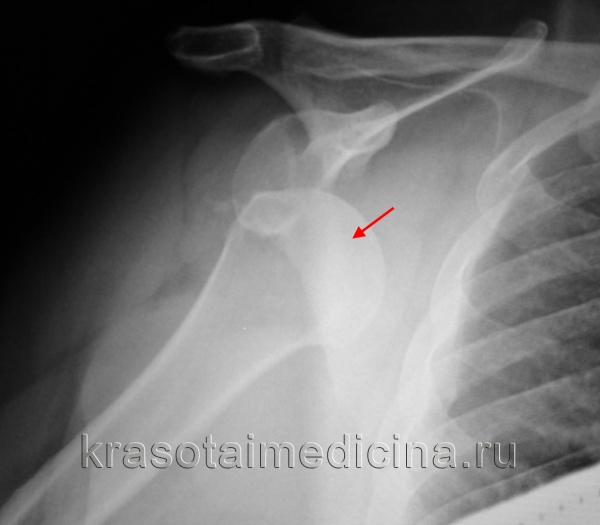

Для уточнения диагноза вывиха плеча и выявления возможных повреждений плечевой кости и лопатки проводится рентгенологическое исследование в двух проекциях. В случае застарелого вывиха плеча может потребоваться МРТ плечевого сустава.

Рентгенография плечевого сустава: вывих головки правой плечевой кости из суставной ямки.